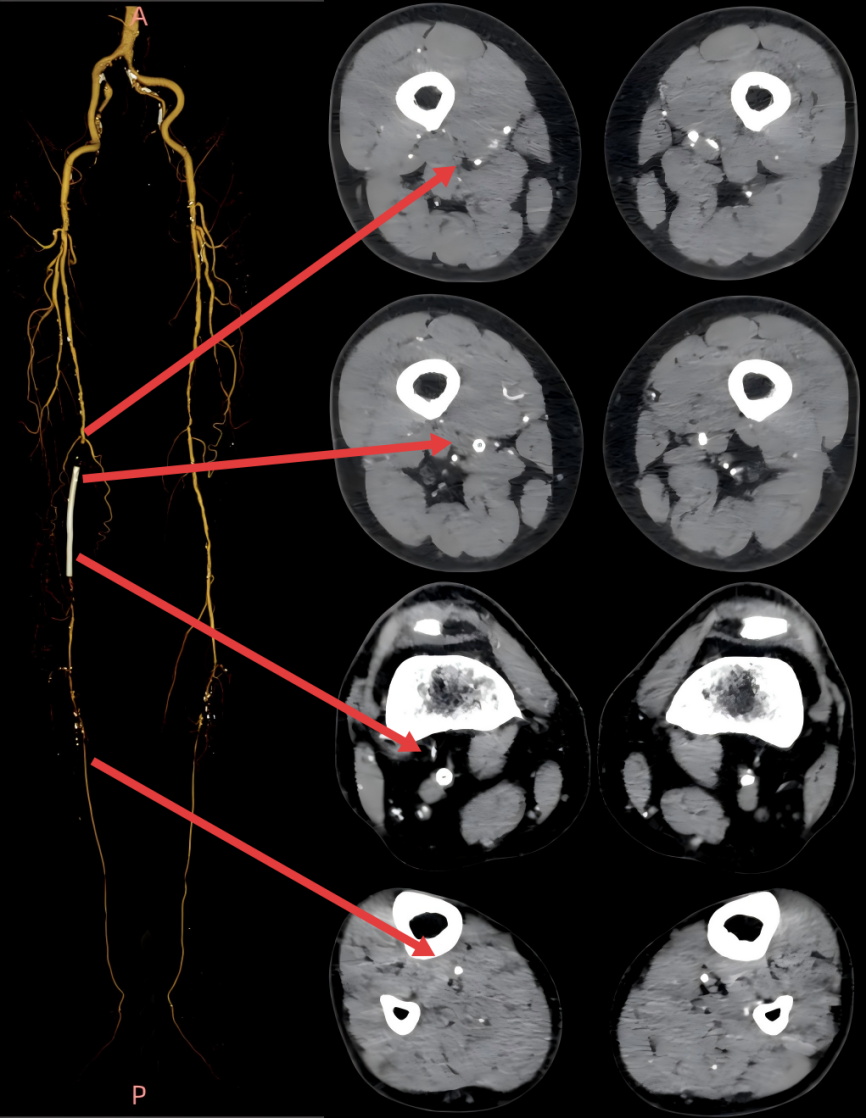

前检查更是触目惊心:下肢动脉CTA显示,李大爷右股动脉支架已完全闭塞,腘动脉还有多处重度钙化狭窄,且仅膝下胫后动脉一条 “流出道”,治疗容不得半点差错。

经过周密的术前评估(结合下肢动脉 CTA、ABI 血管功能检测)和多轮讨论后,血管外科姜坤主任团队为李大爷开展微创介入手术,全程在影像引导下精准推进:

▲术前血管造影与CTA相符

▲采用导丝通过支架内闭塞段顺利,考虑为内膜增生合并部分陈旧性血栓病变,再次造影明确病变长度。

▲血管斑块旋切系统逐段旋切抽吸病变段。

▲造影提示治疗效果良好,成功开通闭塞段。

▲Blades Up模式再次抽吸病变段,股腘动脉管腔获得满意,膝下胫后动脉、足部血流灌注同前,未见明显栓塞。

▲股浅、腘、胫后动脉经POBA+5*300 先瑞达DCB球囊扩张。

▲治疗完毕,最终造影结果,股浅动脉局部非限流性夹层,支架内、膝下流出道血流速满意。